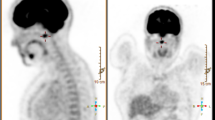

Giant-cell tumours of the spine are very rare. They occur mainly in long bones. We report a patient with a giant-cell tumour of the lumbar spine which had been operated on at another hospital 5 months previously as a protruded lumbar intervertebral disc.

Inci, S., Akbay, A. & Bertan, V. Giant-cell tumour of the lumbar spine. Case report. Spinal Cord 31, 412–414 (1993). https://doi.org/10.1038/sc.1993.69